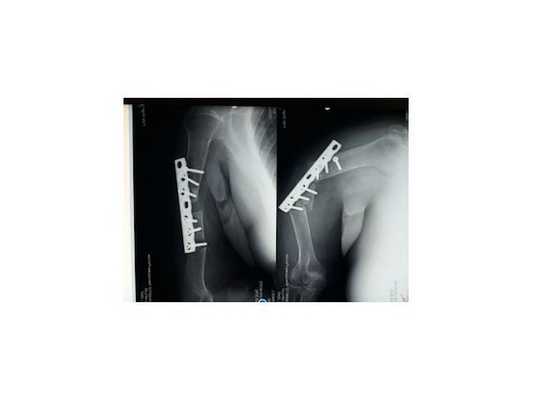

1. Больной Г., 19 лет, поступил через 4 мес после травмы и операции с диагнозом: несрастающийся перелом нижней трети диафиза правой плечевой кости после остеосинтеза пластиной; нестабильность металлофиксатора (рис. 1). Рисунок 1. Рентгенограммы больного Г., 19 лет (I), и функция конечности через 2,5 года после реконструктивной операции (II). I: а - оскольчатый перелом плечевой кости, б - накостный остеосинтез пластиной, в - через 4 мес после травмы (отсутствие консолидации, несостоятельность остеосинтеза), г - после реконструктивной операции, д - через 3 мес после операции, е - удаление имплантата, ж - восстановление структуры плечевой кости в отдаленном периоде; II: з - состояние мягких тканей плеча, и, к - полное восстановление функции конечности.